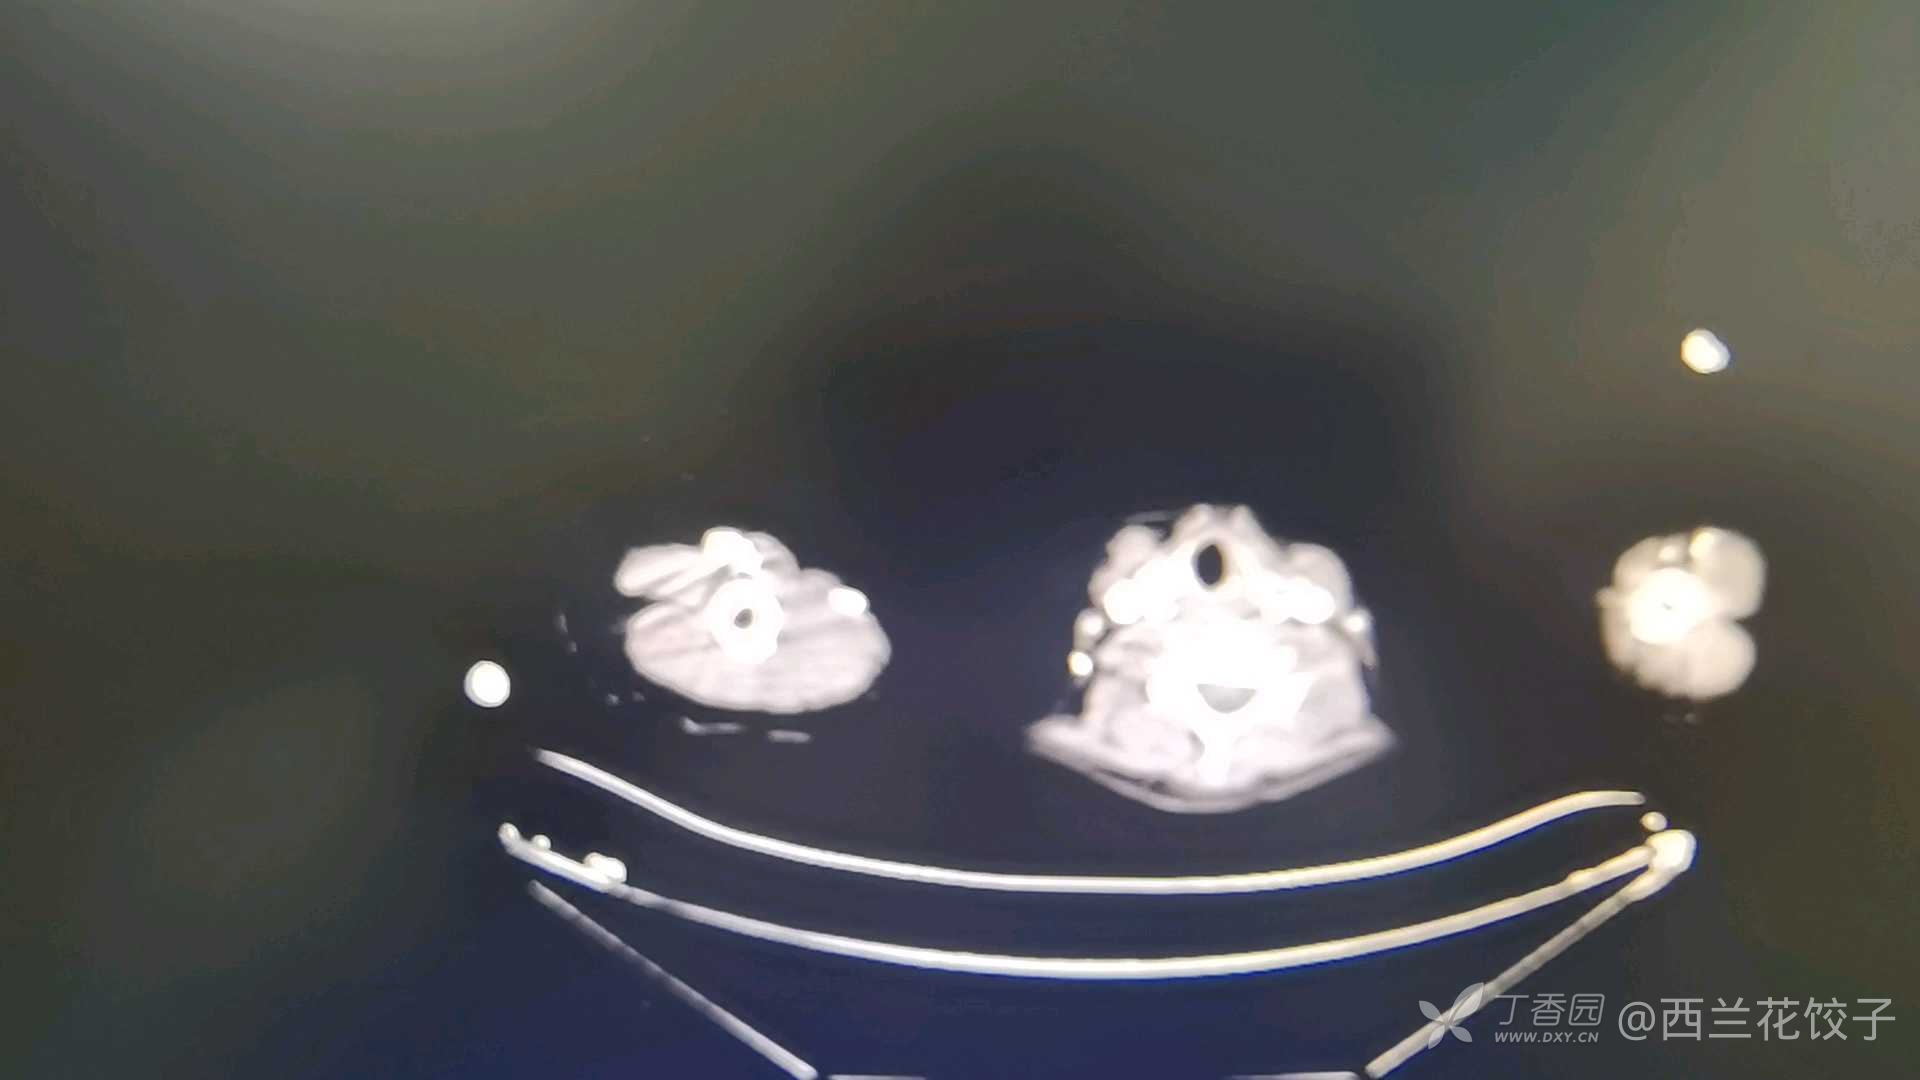

辅助检查:胃镜检查如下,食管内可见大量食物残渣及液体,胃腔内未见明显异常,胸腹部Ct如下,新冠核酸阴性。